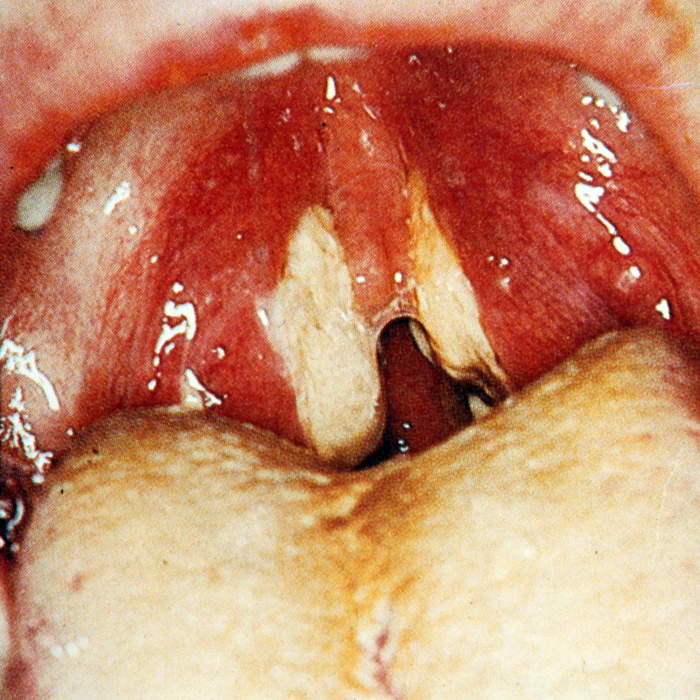

Figure 1.

Unilateral enlargement of the tonsil. A rare indication for tonsillectomy to out-rule lymphoma.

- Asymmetrical tonsil (See Figure 1)